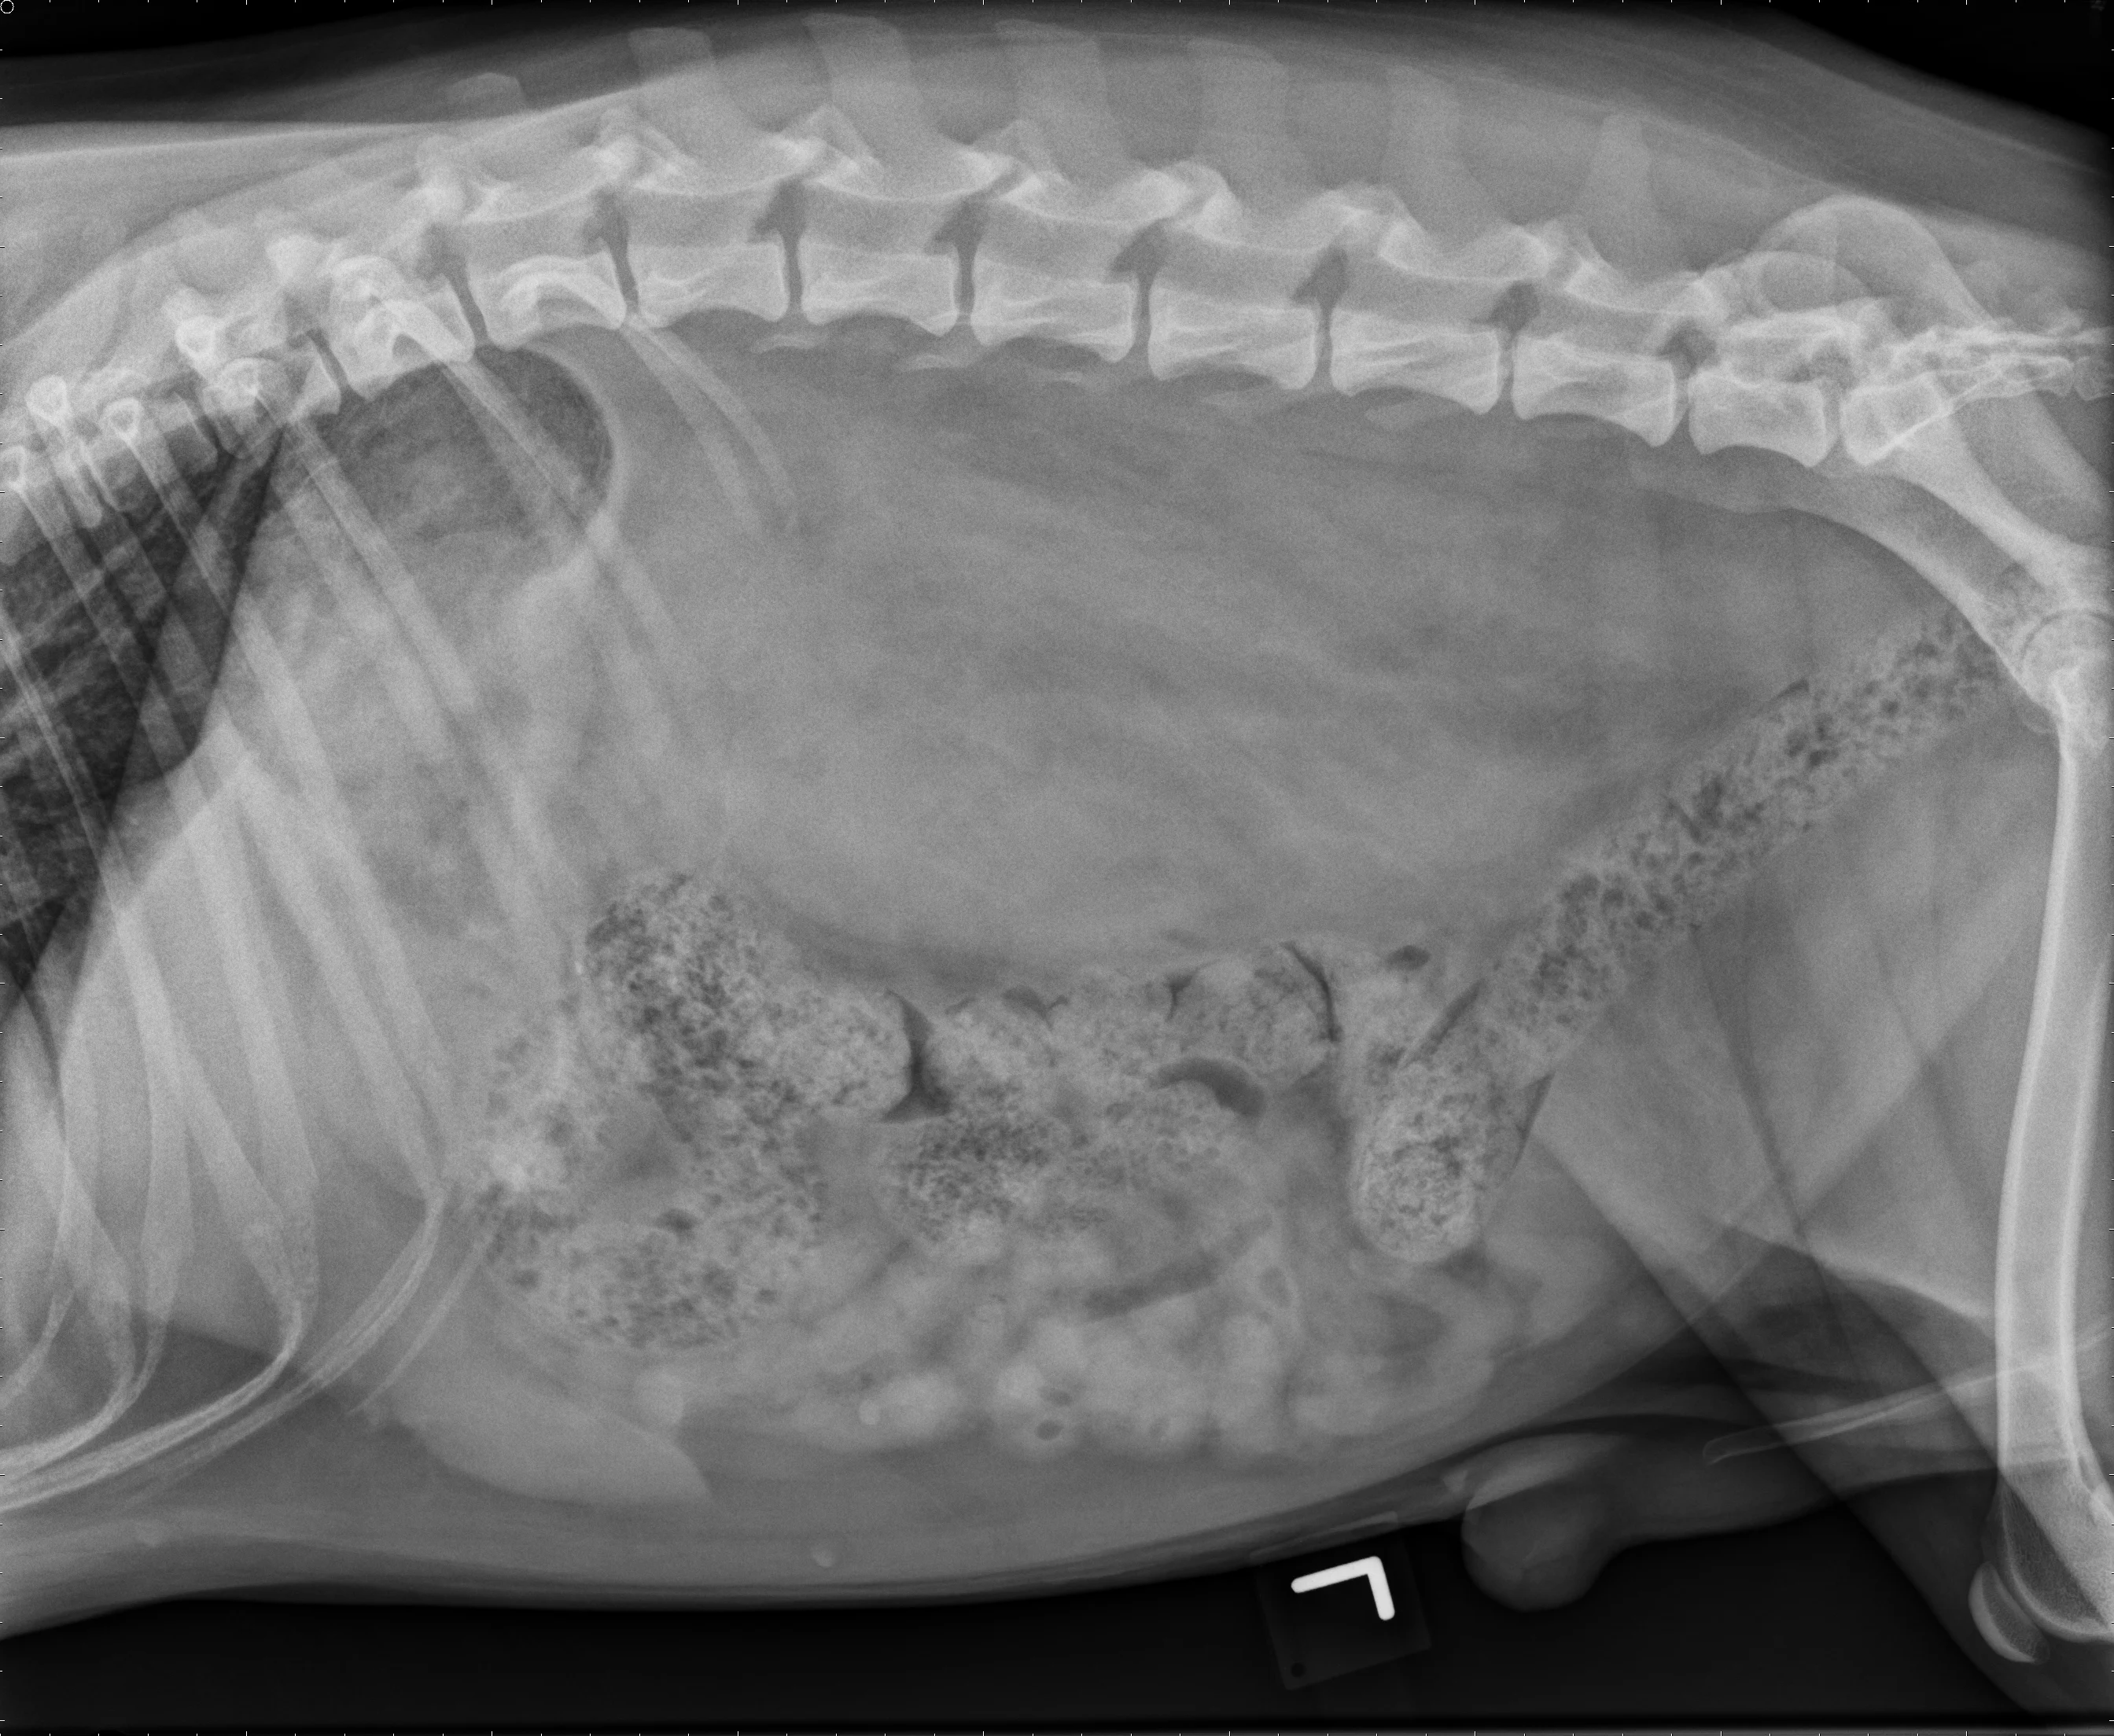

Retroperitoneal effusion in a dog